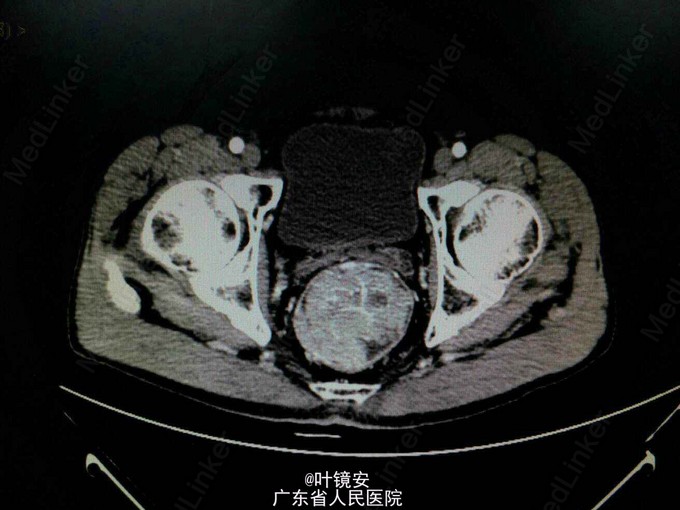

查体:生命体征平稳,心肺无明显异常,腹平软,无压痛以及反跳痛。肛门指检:胸膝位距肛门5cm可触及1点处有一肠腔内肿物,质软,可见5、7、9点有痔核,粘膜轻度出血,退指指套染血。辅助检查:全腹+盆腔CT检查提示:直肠肿块,考虑直肠癌可能性大,并有直肠系膜内淋巴结转移,请结合肠镜检查。内镜:距肛门5cm一巨大肿物,表面呈结节状,活检提示绒毛管状腺瘤改变,伴高级别上皮内瘤变。肛门可见痔核。

诊断:1.直肠肿物:高级别上皮内瘤变? 2.内痔 处理:拟行腹腔镜下miles术